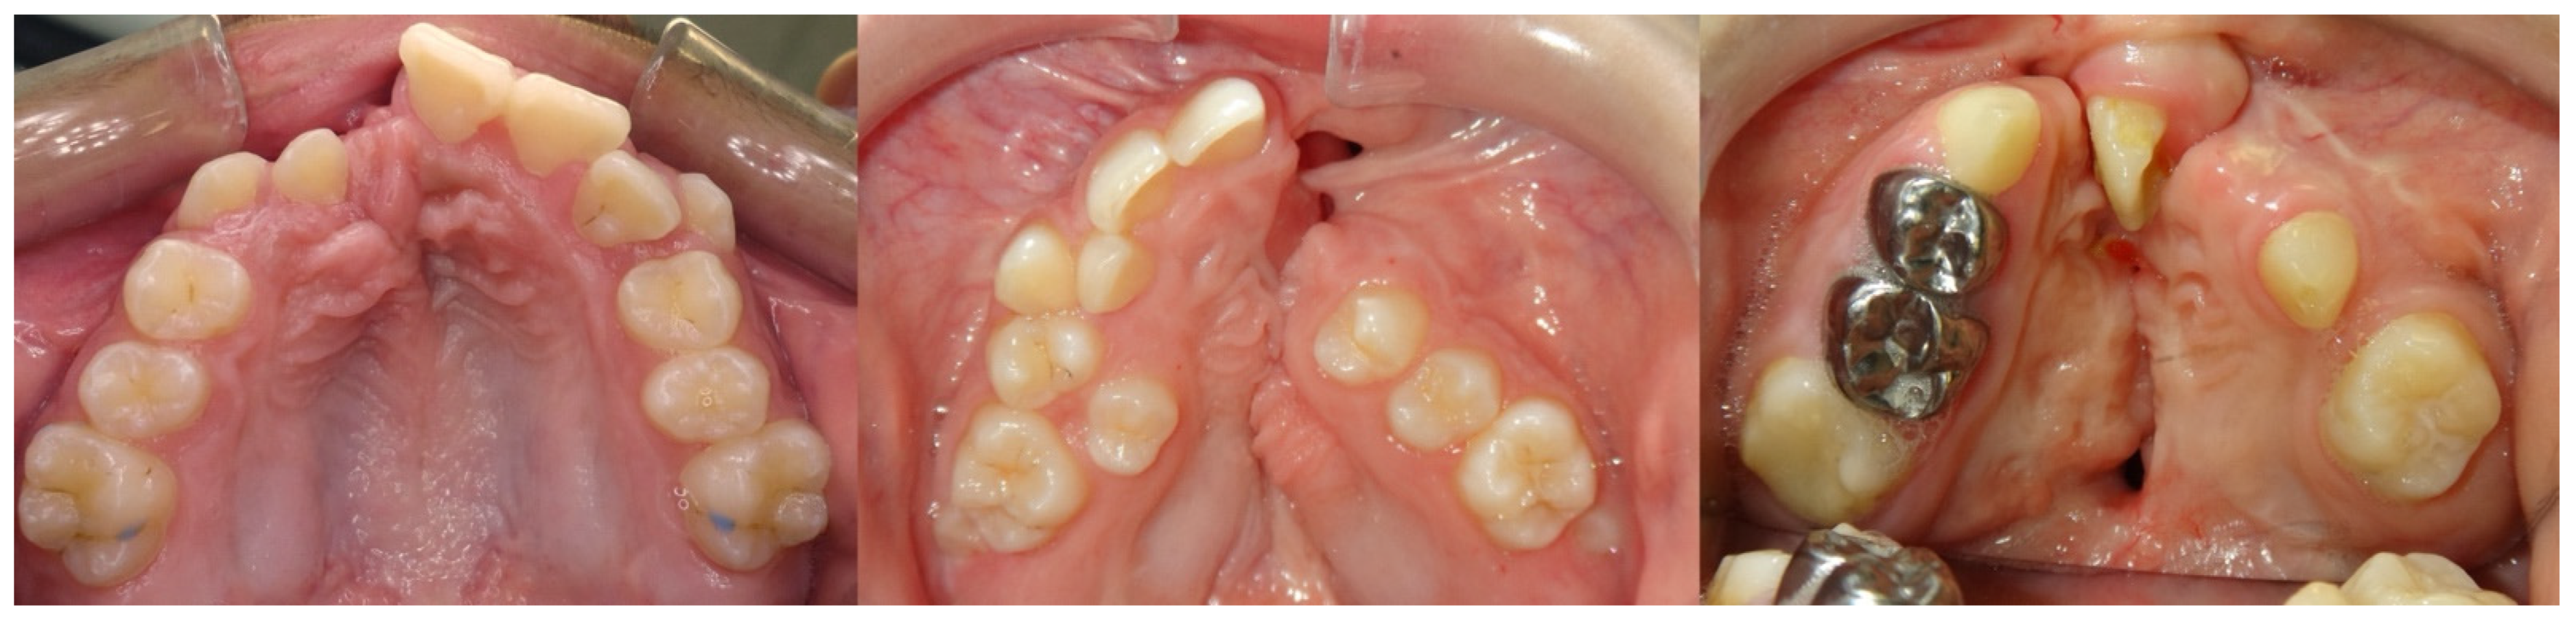

2. Case Description